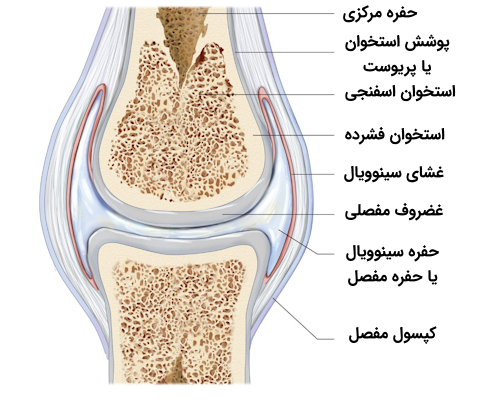

با در نظر گرفتن این دو عامل باید بگوییم که زانو در گروه «مفصلهای سینوویال» (Synovial Joint) قرار میگیرد که بیشترین دامنه حرکتی را دارند. این مفصلها به این صورت شکل میگیرند که یک استخوان در حفره موجود در استخوانی دیگر جای میگیرد. برای درک بهتر ماهیت مفصلهای سینوویال به تصویر زیر توجه کنید.

انتهای استخوانهای سازنده مفصل زانو توسط پوشش غضروف شیشهای یا «غضروف هیالین» (Hyaline Cartilage) که ساختاری لغزنده دارد، پوشیده میشود. به منظور کاهش اصطکاک میان استخوانها، فضای میان دو استخوان با غشایی پوشیده میشود که به آن «غشای زلالی» یا «غشای سینوویال» (Synovial Membrane) میگوییم. این غشا در حقیقت کیسهای است که مایعی خاص با قابلیت محافظت از مفصل زانو در آن وجود دارد.